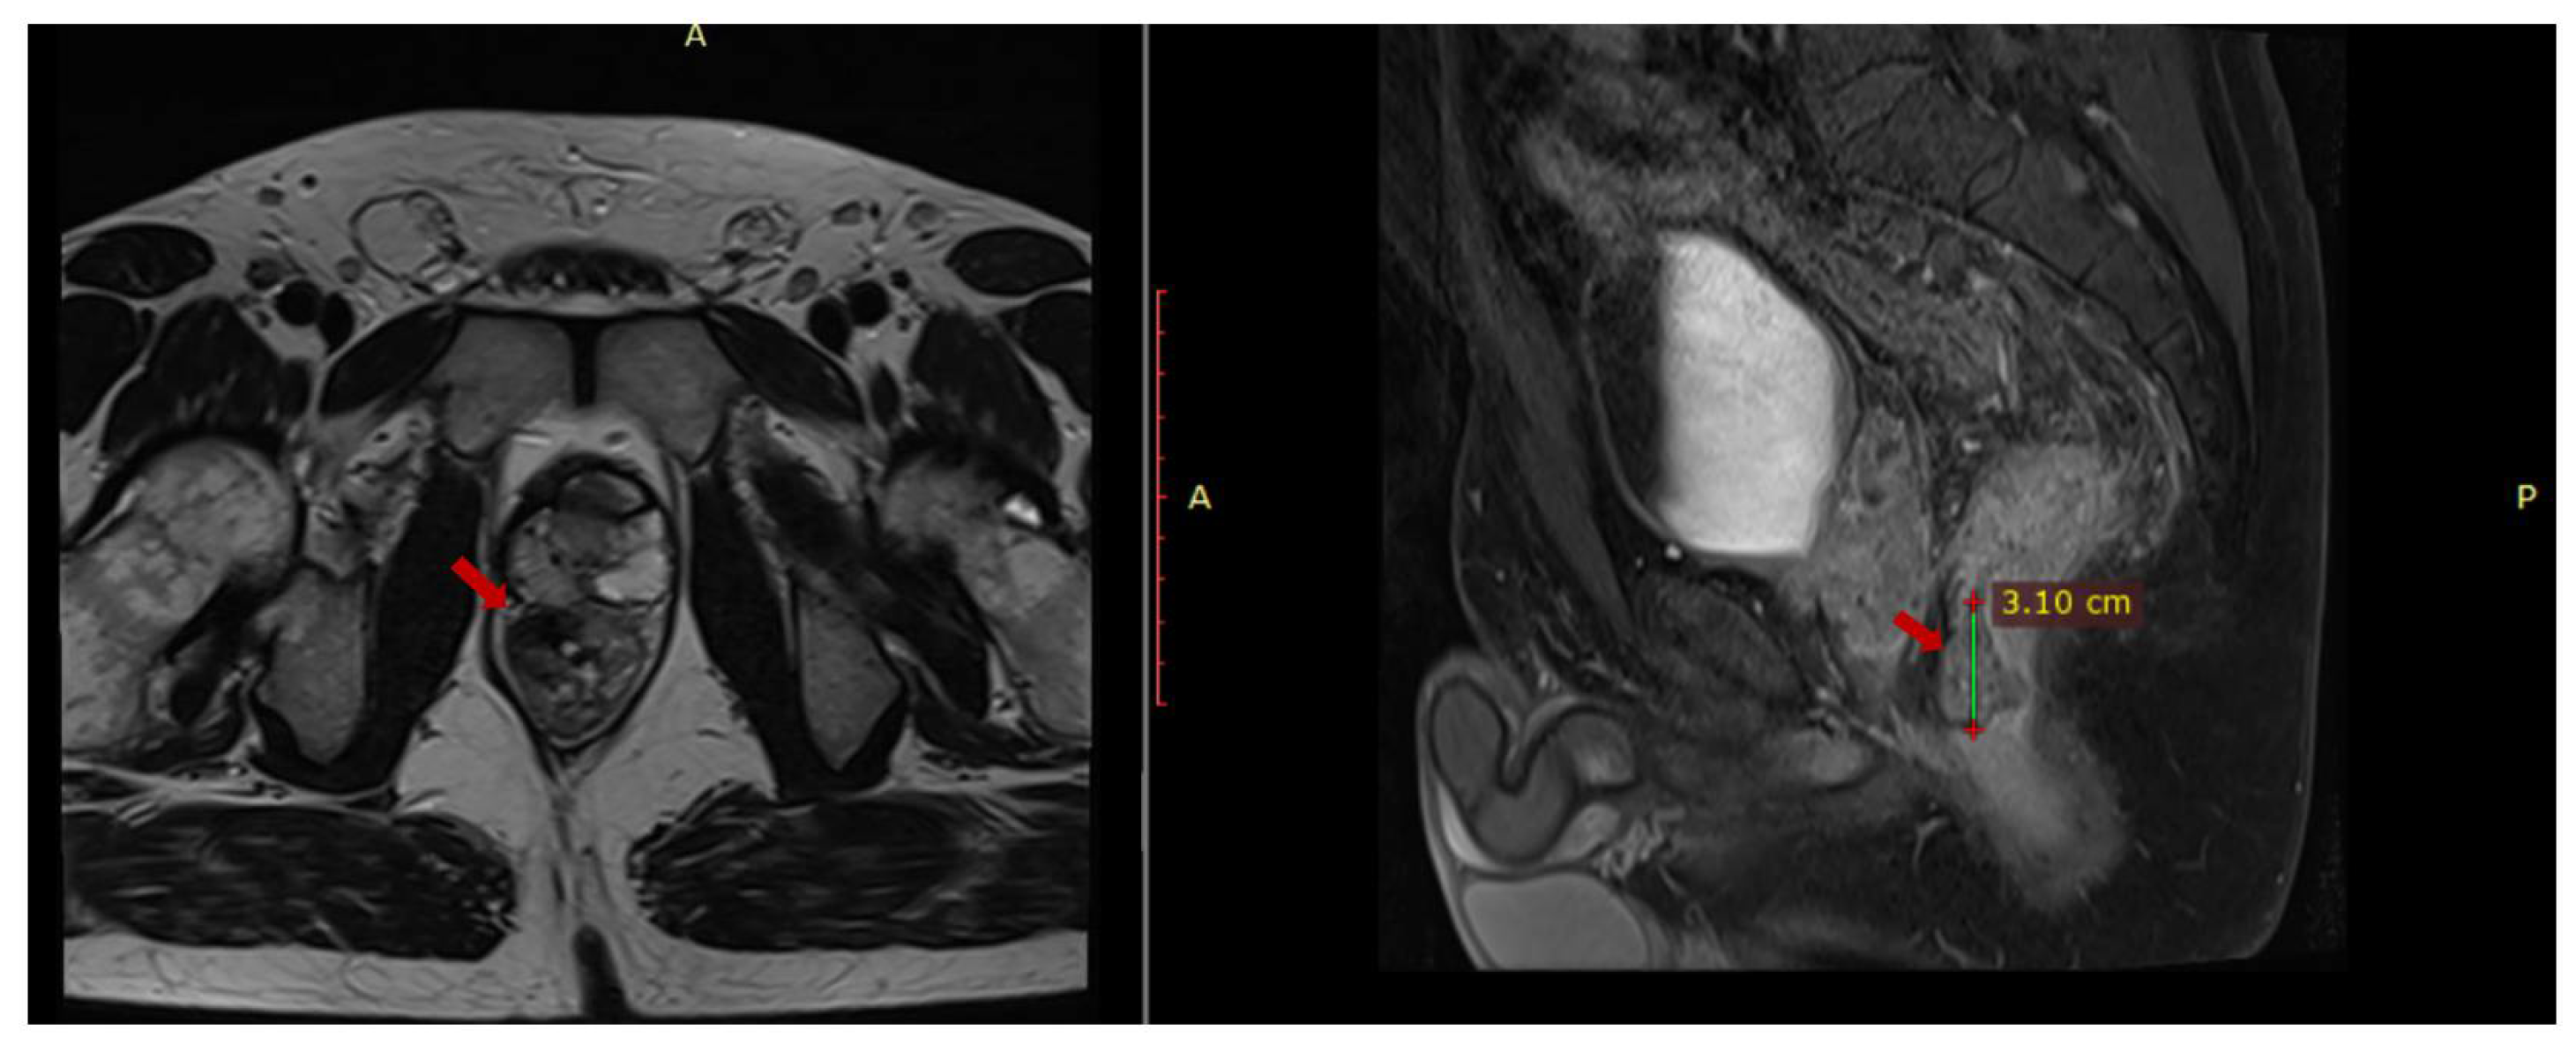

An abdominal and pelvic MRI was performed in March 2023 and it identified circumferential parietal thickening of the rectal wall (1.2 cm), a fibrous lesion with microcalcifications (2.8 × 1.47 × 3.08 cm) adherent to the prostate, multiple mesorectal lymphadenopathies (up to 1.25 cm) and (1.97 × 0.87 × 1.7 cm) thick fluid collection located in contact with the anterior portion of the prostate (Figure 1).

Figure 1.

Pelvic MRI axial T1 and sagittal T2 sequences depict contrast-enhanced fibrous tissue in the rectum that adheres to the prostate.